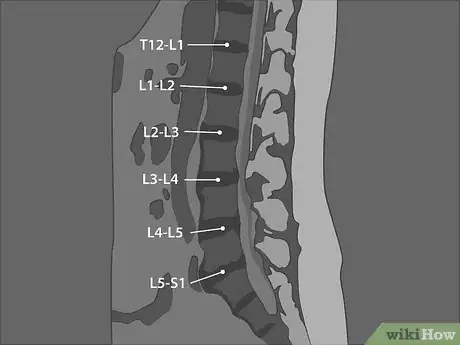

2Label the discs between the vertebrae. Each of the vertebrae of your lumbar spine is separated by a disc that acts as a cushion for the vertebrae. Your discs keep the bones of your spinal column from rubbing against each other when you move. They are labeled using the number of the vertebrae above and below them, separated by a hyphen.[7]

- For example, the disc between the third lumbar vertebra and the fourth lumbar vertebra is referred to as L3-4. Looking at your sagittal image, you should be able to determine the name for each of the discs in the lumbar region of your spine.

- The disc under L5 sits between the last vertebrae of the lumbar region and the first vertebrae of your sacrum, so it is referred to as L5-S1.